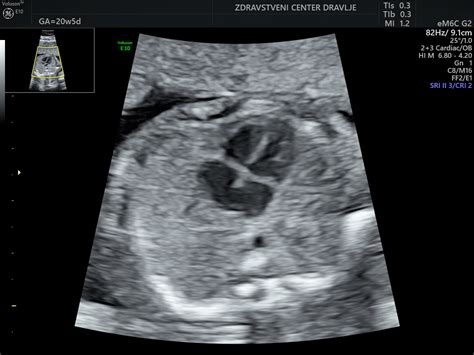

Ultrazvočni pregled nuhalne svetline se običajno izvaja preko trebuha, le izjemoma vaginalno, če je položaj ploda neugoden ali je nosečnica predebela. Primeren čas za preiskavo je, ko je plod velik med 45 in 84 mm, kar ustreza približno 11 3/7 do 14 tednov nosečnosti. Med pregledom zdravnik natančno določi predvideni dan poroda in oceni zgodnji razvoj ploda. Poleg debeline nuhalne svetline preveri tudi pravilnost razvoja trebušne stene, možganov, okončin in drugih notranjih organov.